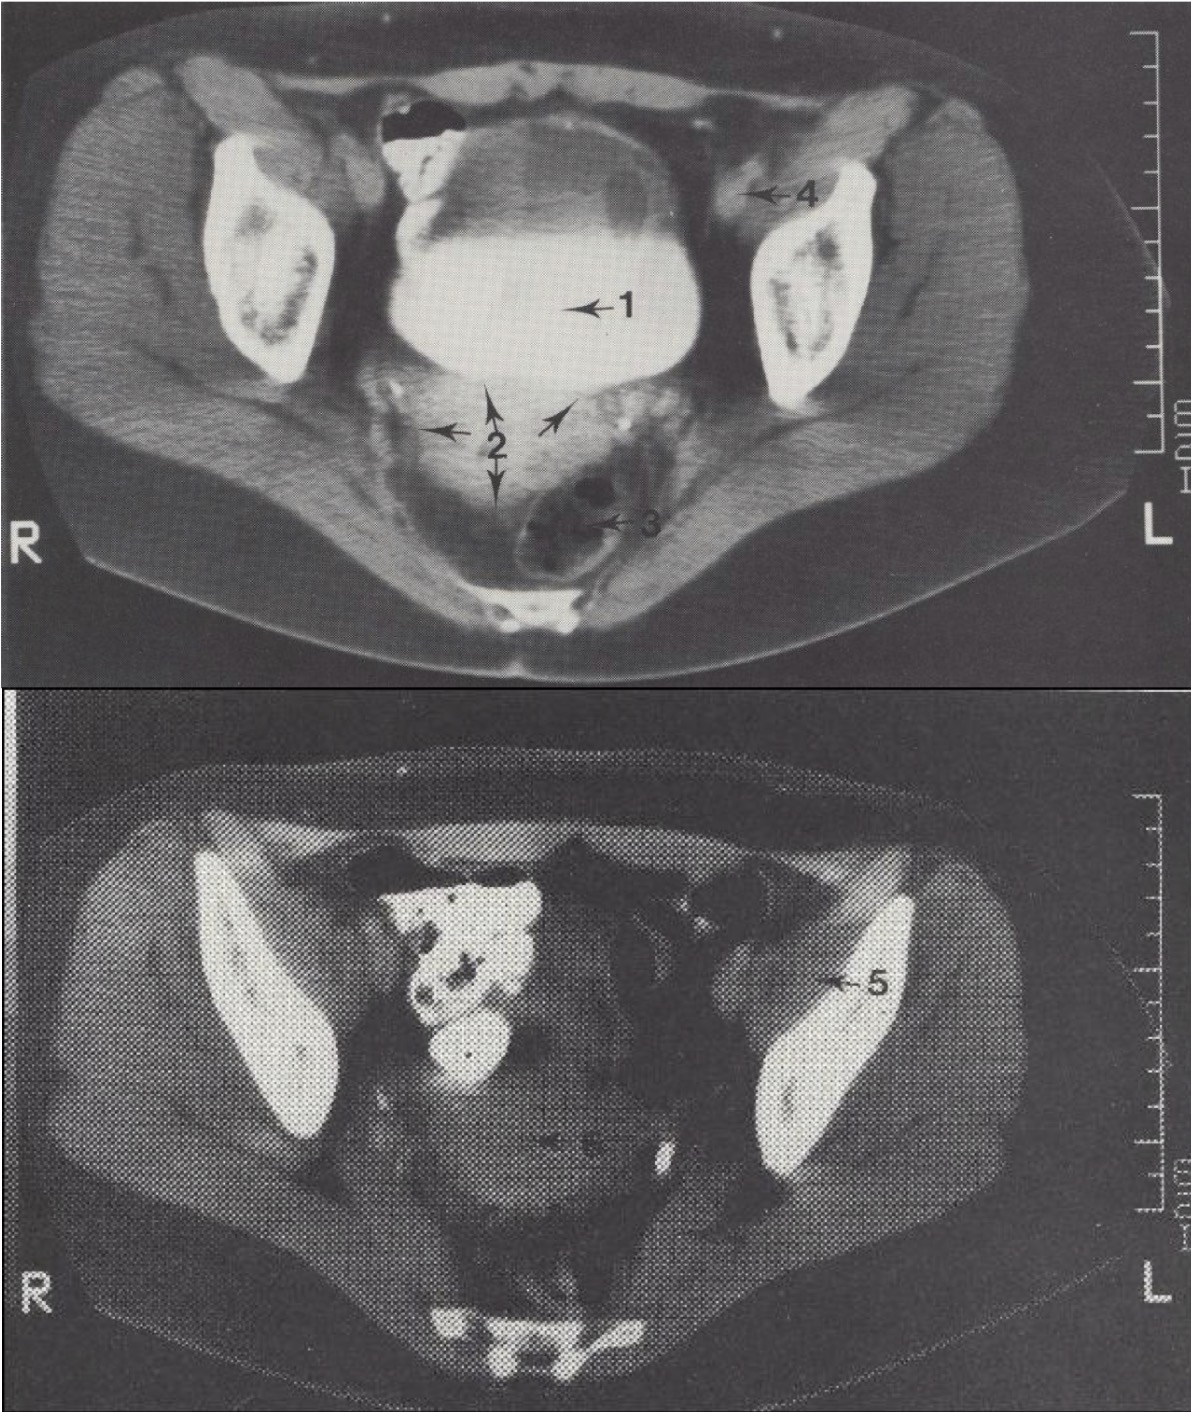

5

M. iliopsoas (klubinis juosmens raumuo)

Metodika

KT pjūviai atlikti virš acetabulum (gūžduobės). Naudotas intraveninis kontrastas (šlapimo takams) ir peroralinis kontrastas (žarnyno kilpoms).

Svarbu

Pacientei gulint, šlapimo pūslėje matomas kontrasto išsisluoksniavimas: sunkesnis jodo kontrastas nusėda apačioje, o lengvesnis šlapimas – viršuje.

Topografija

Gimdos šešėlis (corpus uteri) matomas tarp tiesiosios žarnos (rectum) ir šlapimo pūslės (vesica urinaria).